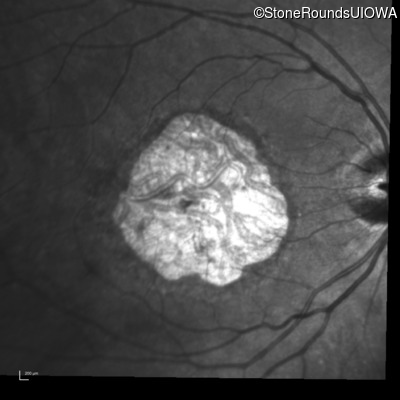

Infrared Fundus Photograph - Right - 20/125

Exemplar